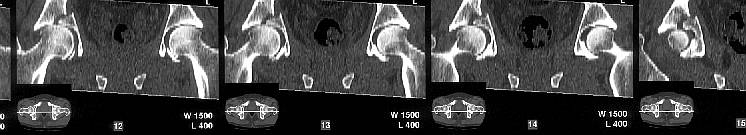

The CT scan confirms what the iliac oblique showed - the acetabulum is incongruous, and the femoral head is following the caudal piece medially. The other thing the femoral head is doing is grinding up against that displaced fracture. This is going to lead to erosion of the femoral head cartilage, and rapid onset of post-traumatic arthritis.

How long will it take? I've seen it happen in less than a year.

Yes it does. The CT scan reveals a fracture through the weight bearing dome.

My mail was based on the first mail from Alo Kullerkann before the CT pictures were avilable on the net. Later I saw the CT pictures and realised that weight bearing areas were involved.